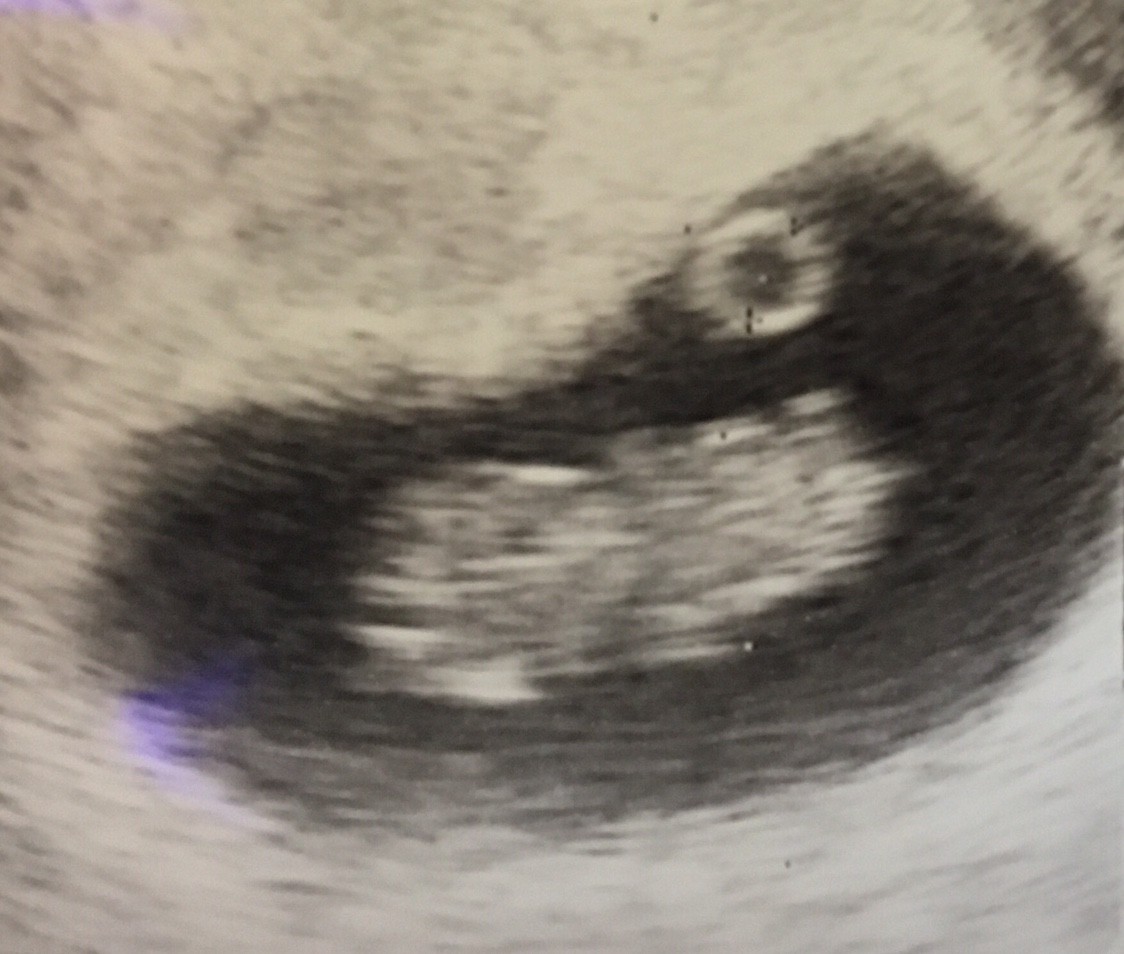

Wróciłam już do domu. Z jednej strony ogromna radość, bo serduszko bije, dzidzia rośnie, a nawet wyprzedza swój wiek wg miesiączki. Ma już 3,1cm i wg usg jest to 10t0d. Super było je zobaczyć chociaż przez pare sekund. Zła wiadomość jest taka, ze krwiak jest dalej... umiejscowienie w miarę „dobre”, ale muszę bezwzględnie cały czas dalej leżeć... no nic trzeba się poświecić, dla dziecka wszystko. Załączam fotki: na jednej dzidzia, a na drugiej z lewej górnej strony widać krwiak.

f2w3rjjghb3ibrut.png